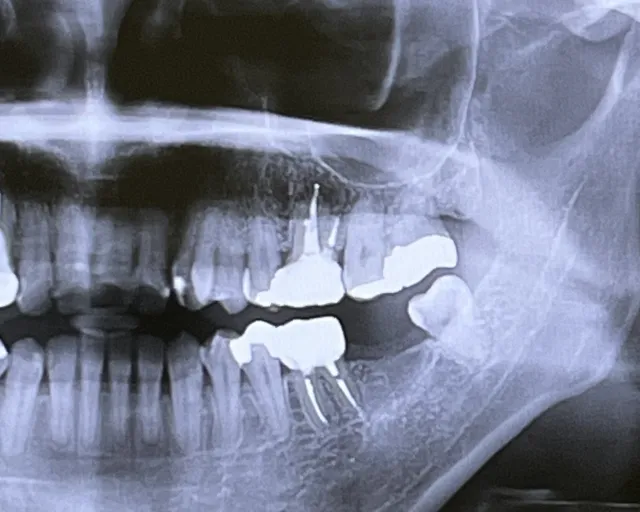

歯の根元付近の歯肉が腫れたり、膿が出たり、またはレントゲン写真で根の先に黒い影(膿の袋:膿瘍)が見られる場合は、神経が死んで細菌感染が根の外にまで広がっている状態です。

この状態を「根尖性歯周炎」や「根尖病巣」と呼び、放置すると顎の骨まで炎症が広がるリスクがあります。最悪の場合、顎や顔面全体の重篤な感染症(蜂窩織炎など)につながることもあり、緊急の治療が必要です。 -

レントゲン写真や視診で、虫歯が神経に非常に近い、または既に到達していると判断される場合も神経治療の適応となります。また、歯に深い亀裂(クラック)が入り、その亀裂が神経腔にまで達している場合も同様です。